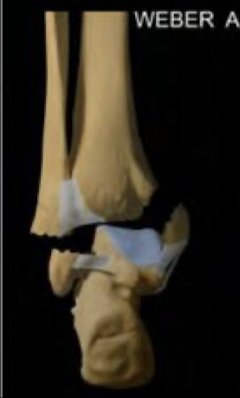

Q

WEBER A

A

fx de peronde por debajo del nivel del plafon tibial